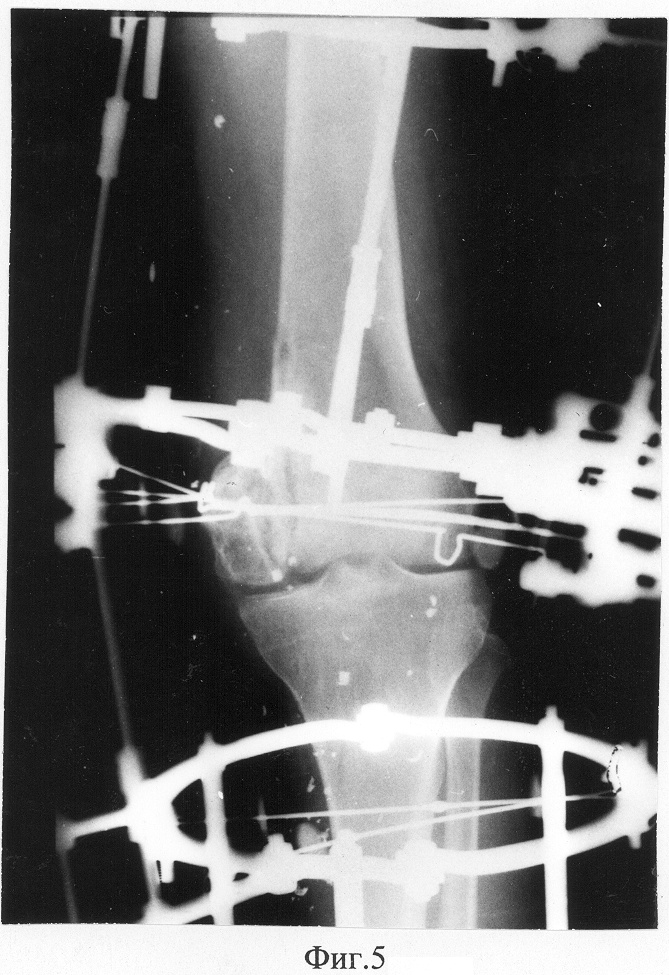

Фиг.5 – рентгенограмма коленного сустава пациента в прямой проекции в процессе лечения;

Под эпидуральной анестезией было наложено устройство для лечения посттравматического гонартроза из 5-ти опор, которые соединяли при помощи стержней и стержней с шарнирами. При этом опора, установленная в проекции мыщелков бедренной кости, не содержала спиц. Была произведена артротомия левого коленного сустава, выполнена остеотомия в проекции плоскости излома внутреннего мыщелка бедренной кости с переходом в проксимальном направлении на метадиафизарную часть внутреннего кортикала бедренной кости. Через сформированый фрагмент внутреннего мыщелка бедра по направлению от его проксимальной части к дистальной вдоль биомеханической оси конечности в сагиттальной плоскости были проведены две дистракционно-направляющие спицы с перекрестом 20°, которые при помощи резьбовых стержней с пазом и шарнирных узлов крепились к дистальной опоре на голени (Фиг.4). Посредством дистракции по стержням, установленным по внутренней поверхности коленного сустава между базовыми модулями аппарата на бедре и голени, выравнивалась щель коленного сустава с одновременным частичным низведением остеотомированного фрагмента внутреннего мыщелка бедренной кости. При помощи дистракционно-направляющих спиц, посредством дистракции по резьбовым стержням с пазом, осуществлялось низведение мыщелка до нормокоррекции. В процессе низведения мыщелка выполняли контрольную рентгенографию, после чего в кософронтальной плоскости через мыщелки бедренной кости были проведены четыре спицы со штопорообразными упорными площадками три – изнутри, а одна – снаружи, которые фиксировались к дистальной опоре на бедре в проекции его надмыщелков при помощи стержней с пазом и кронштейнов. Узлы продольного перемещения мыщелка были демонтированы, дистракционно-направляющие спицы удалены (Фиг.5, 6). Перемещение мыщелка по ширине в плоскости, перпендикулярной оси конечности, осуществляли при помощи спиц со штопорообразными упорными площадками, посредством дистракции по стержням с пазом до восстановления конфигурации мыщелков бедренной кости.